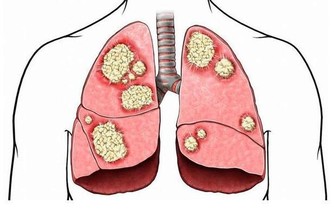

睡前飲酒就更傷肝了。因為,酒精的代謝,會給本應休息的肝臟帶來更多的負擔。酒精對肝臟的危害是逐步累積的,隨著量的增加和時間的延長,酒精代謝產生的乙醛會在肝臟不斷積累,引發炎症和肝功能損傷,甚至發展成酒精性肝硬化、肝癌。所以說,酒能少喝就少喝,當然,不喝更好。更別通過喝酒來助眠、養生,真的得不償失!